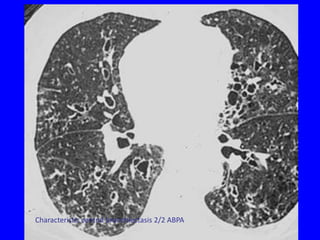

Characteristic central bronchiectasis 2/2 ABPA

Note characteristic location in the upper lobes and superior segments of

lower lobes

• 97.

• 98.

Note characteristic locationin the upper lobes and superior segments of lower lobes